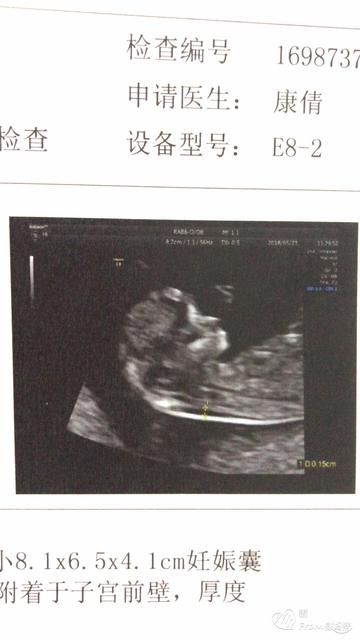

从妊娠月经的第一天开始算起,7天位一个妊娠周,28天为一个妊娠月。您的末次月经是7月18号,预产期是2012年4月25号。建议您保持愉快的心情,如果在怀孕k1